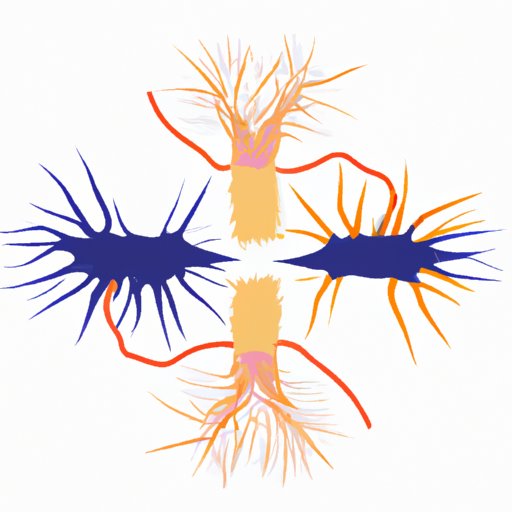

The Science Behind Hydrophobia: Why Does Rabies Cause Fear of Water?

Explore the fascinating and complex link between rabies and hydrophobia, a symptom that causes intense fear of water. Discover the mechanism behind hydrophobia, the science that explains it, and why it’s important to understand the connection between rabies and hydrophobia. Learn how the immune system and areas of the brain responsible for regulating emotions contribute to the development of hydrophobia, and what can be done to manage the symptoms.